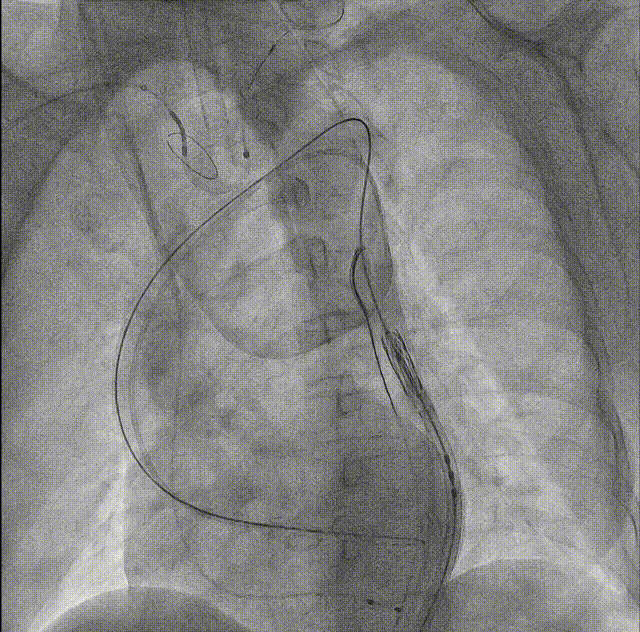

术前经团队讨论,可调弯系统、短瓣架的球扩瓣更适合该解剖结构,拟经右侧股动脉入路,为保证顺利跨瓣,术前左侧入路先放置圈套器。选用18mm球囊预扩,MuguetA™21 mm瓣膜90/10-80/20释放,降低术后残余瓣周漏风险,释放后结合造影和超声情况进行综合评估。出于患者钙化重、卒中风险高的特点,决定术中使用SENTINEL抗栓塞脑保护装置为患者保驾护航。

Sentinel捕获的碎片

超声提示微量瓣周漏,瓣膜工作良好,最大跨瓣流速2.02m/s,平均压差6mmHg。

输送系统可调弯系统提高了过弓跨瓣的流畅度,术中团队配合默契,操作熟练,成功将瓣膜在最佳位置释放;输送系统进入到撤出仅耗时20分钟。术后即刻心超提示,瓣膜工作稳定,无反流,微量瓣周漏,植入效果理想。